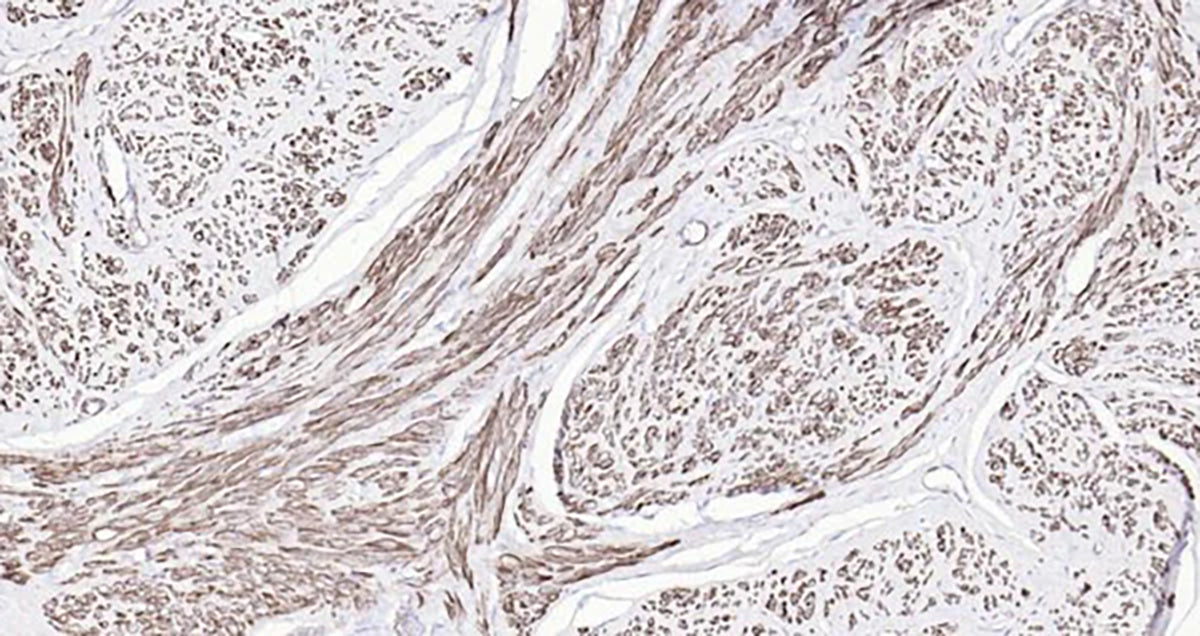

Bioss Ready-To-Use

IHC Kits

Perfect for quickly and conveniently obtaining high-quality IHC data. These kits contain all the needed reagents, primary and secondary antibodies, AND a positive control slide to confirm your staining.

With our optimized protocol, simply use the reagents directly on your tissue sample, and you are ready to gather your data for analysis.